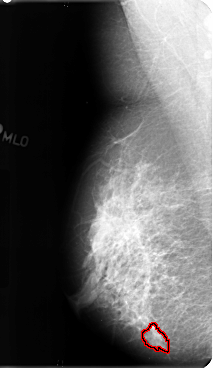

B_3128_1.RIGHT_MLO

RIGHT_MLO LINES 4776 PIXELS_PER_LINE 2768 BITS_PER_PIXEL 12 RESOLUTION 50 OVERLAY

FILE: B_3128_1.RIGHT_MLO.OVERLAY

TOTAL_ABNORMALITIES 1

ABNORMALITY 1

LESION_TYPE MASS SHAPE IRREGULAR MARGINS ILL_DEFINED-SPICULATED

ASSESSMENT 4

SUBTLETY 3

PATHOLOGY BENIGN

TOTAL_OUTLINES 1

BOUNDARY